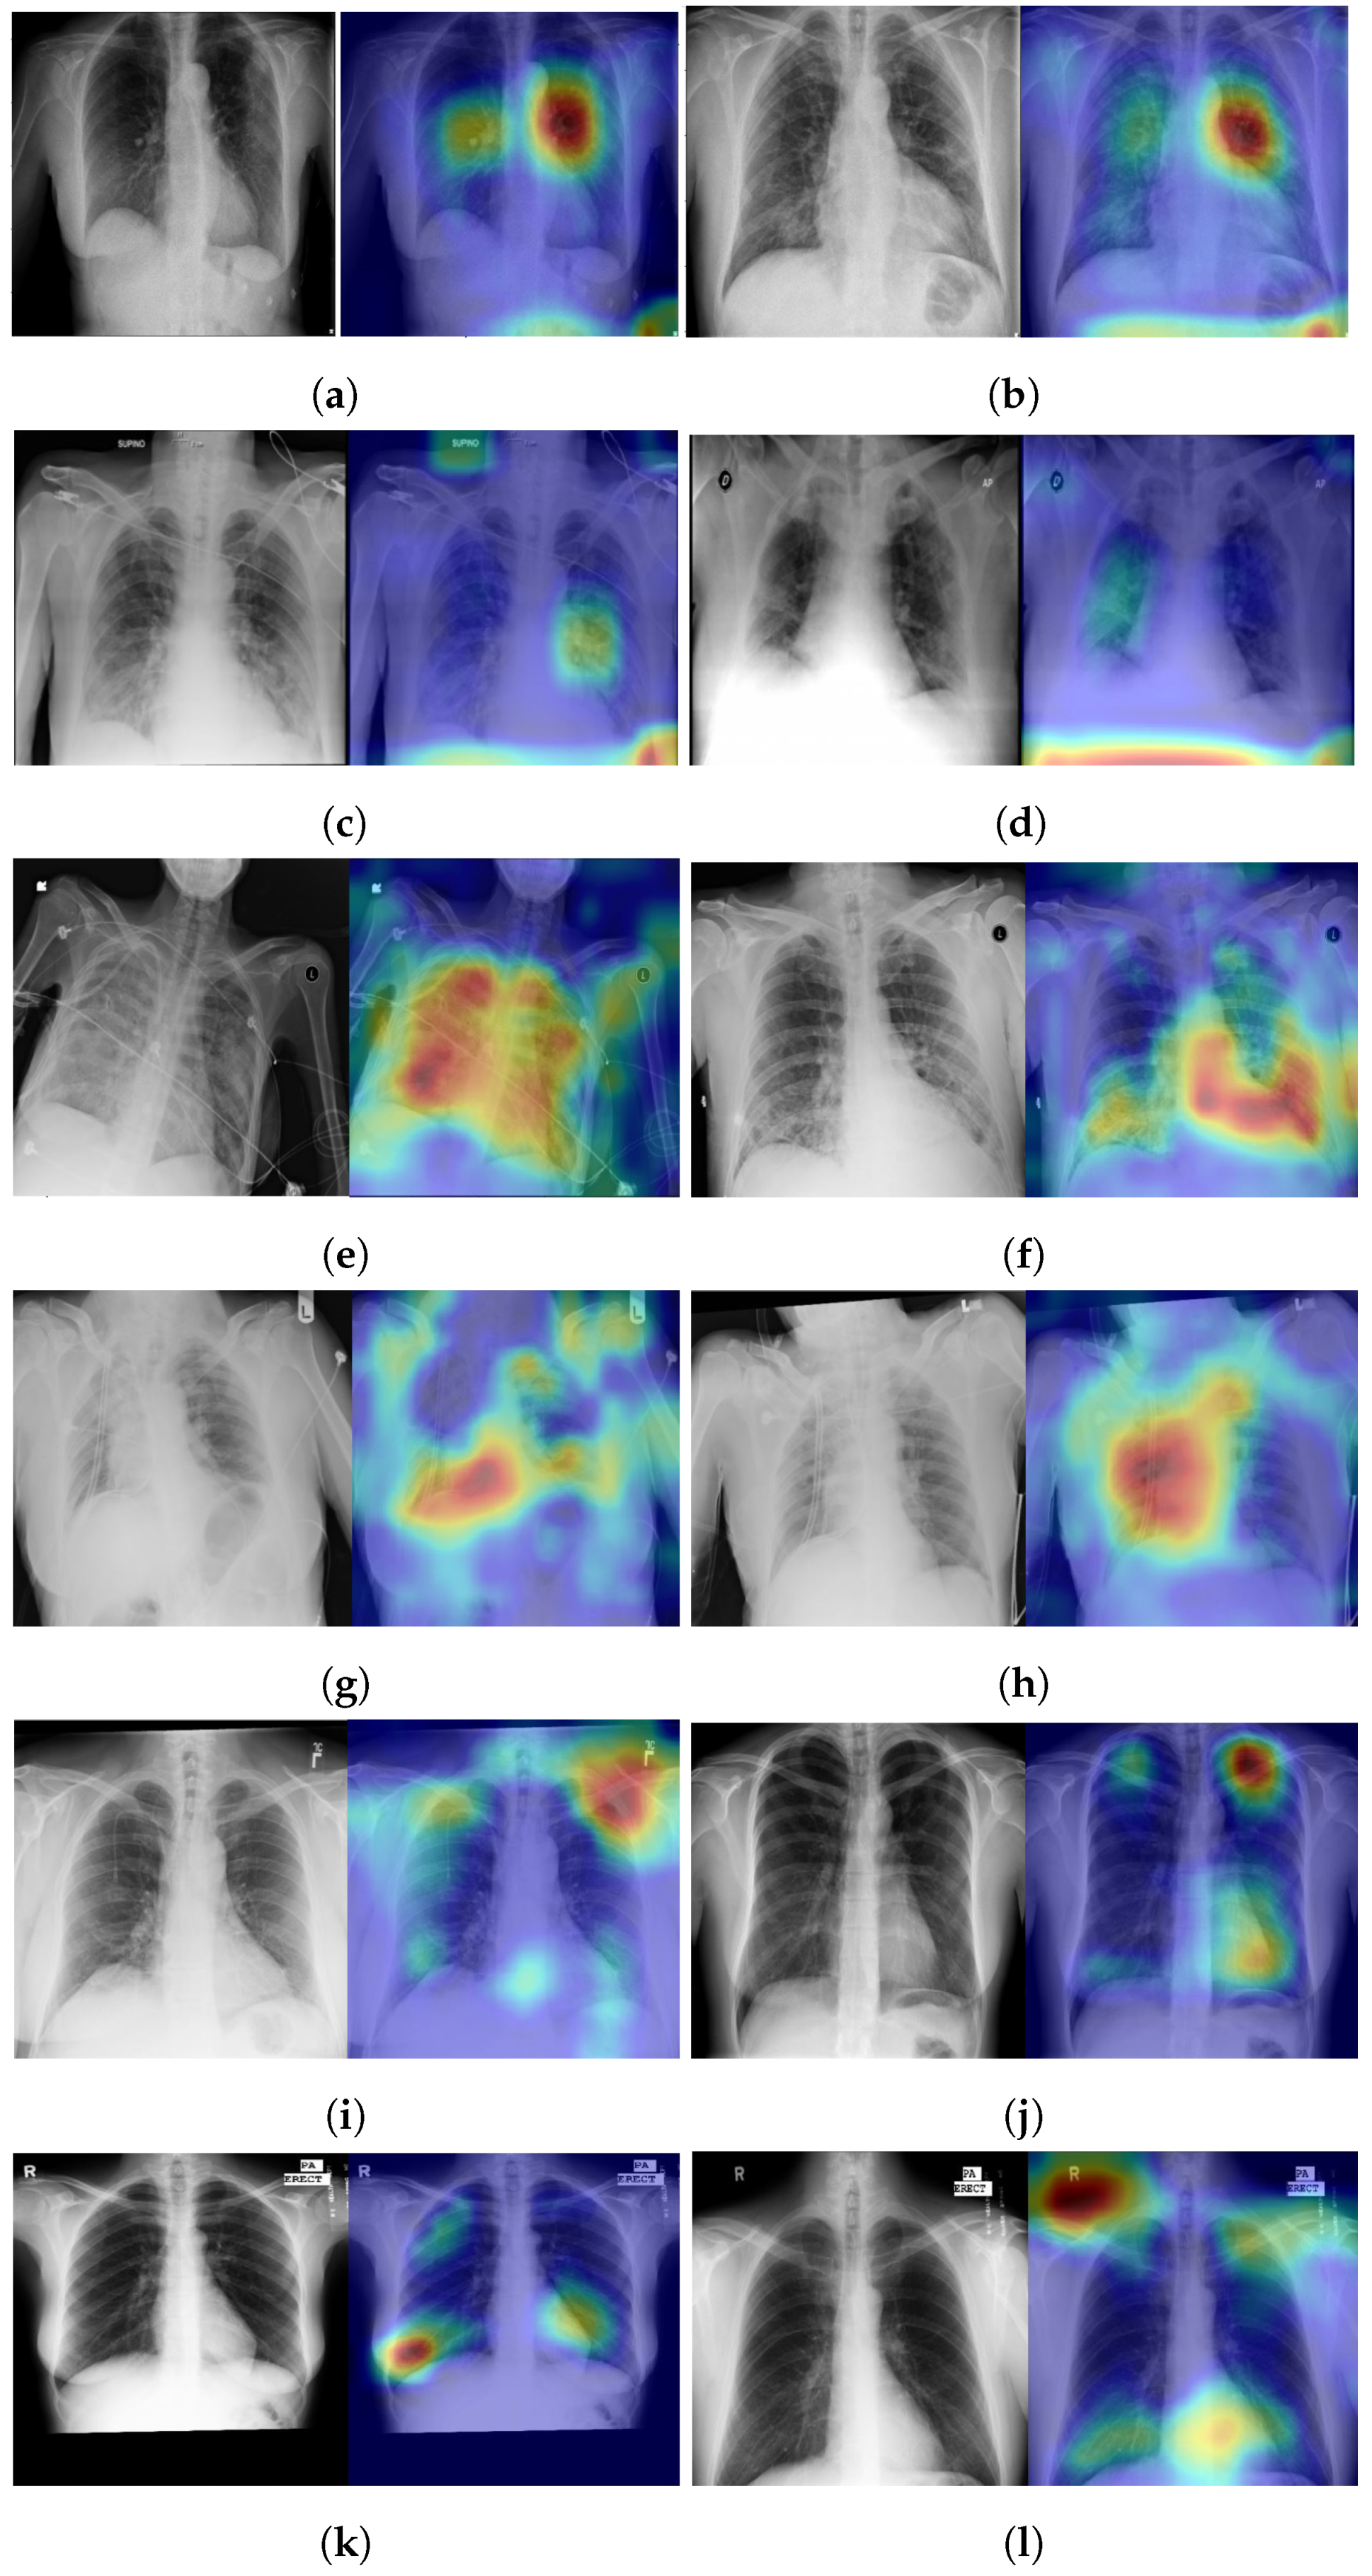

4.5. Explainability